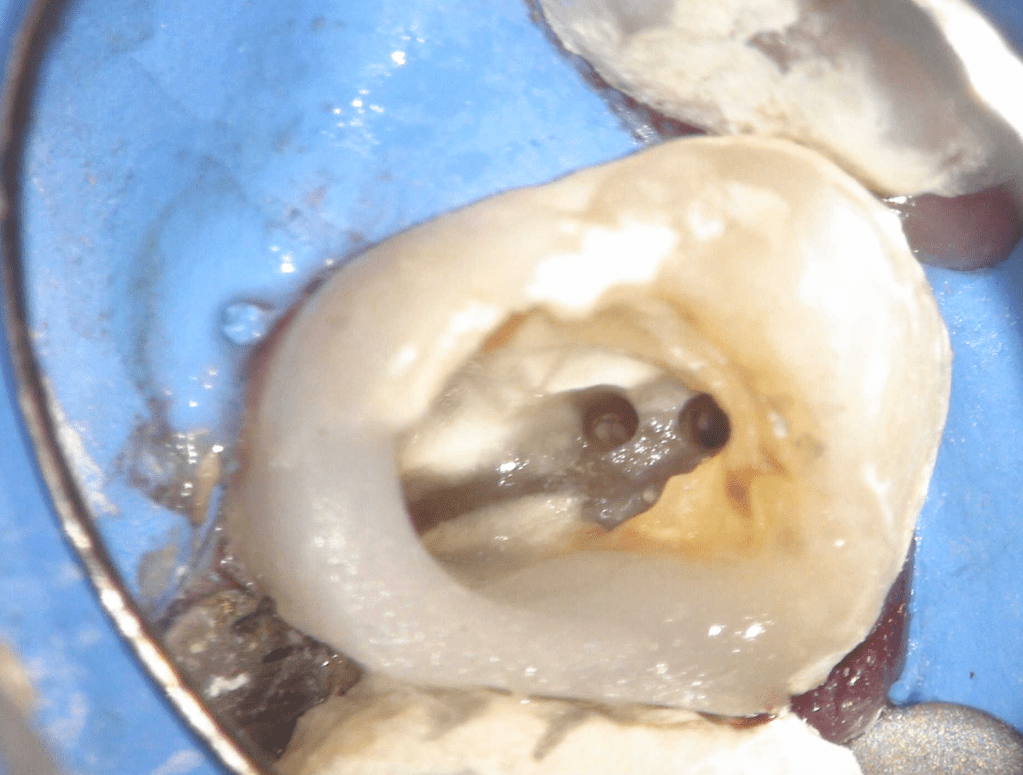

Localización 4o Conducto